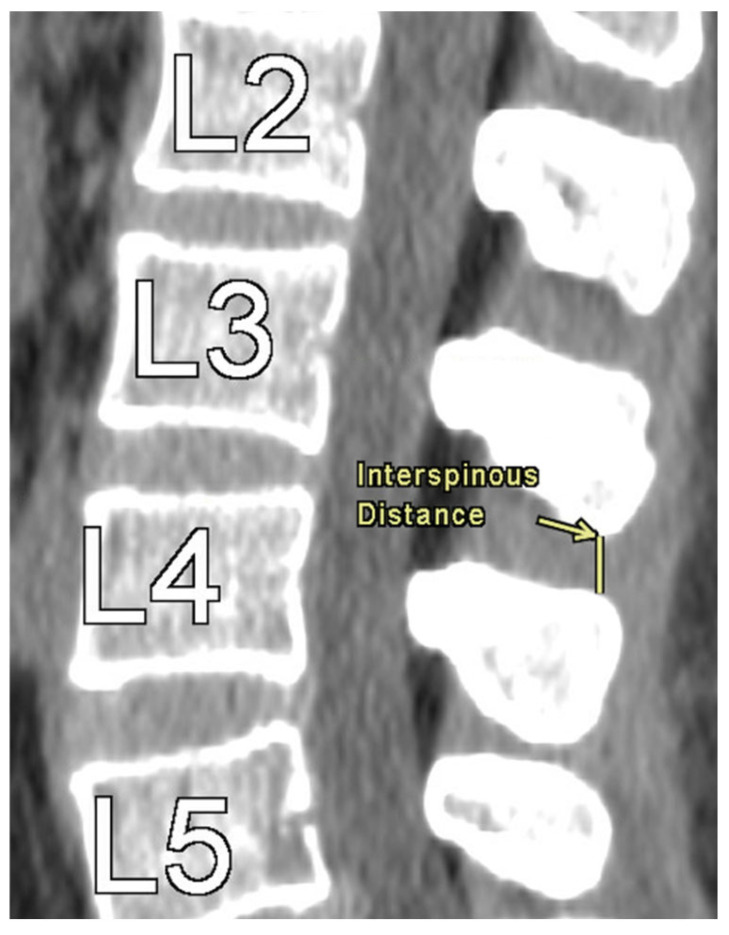

Methods: A retrospective chart review was performed on 852 patients who underwent CT imaging of the lumbar spine. ISD was measured from L1 to L5 as the shortest distance between the most caudal tip of the superior spinous process and the inferior spinous process. DSH was measured at the anterior, middle, and posterior margins. NFDs were assessed in axial and sagittal views, including axial width, craniocaudal height, and foraminal area. Statistical analysis assessed correlations between ISD, NFDs, DSH, and demographic variables.